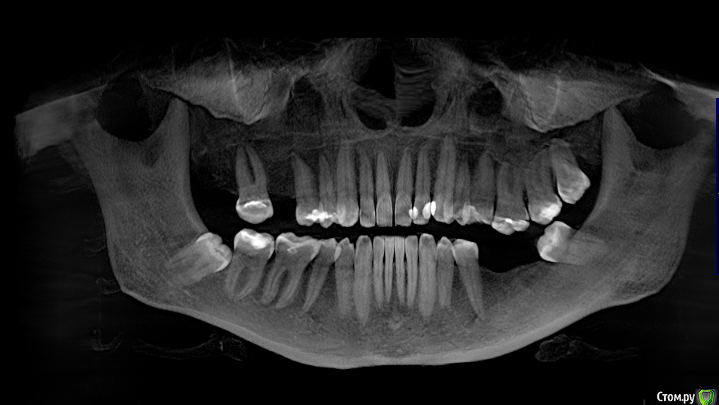

Mariia Опубликовано 9 ноября, 2017 Поделиться Опубликовано 9 ноября, 2017 Уважаемые доктора, добрый день!Посоветуйте, пожалуйста, что можно сделать в моем случае. Давно нет 3-х зубов (более 10 лет), стали стираться 7-ки справа, верхняя 6-ка слева стала опускаться.После нескольких консультаций окончательно запуталась в планах лечения.Понятно, что необходимо устанавливать 3 импланта, но как это сделать? - предлагают ортодонтическое лечение на верхней 6 справа (ставить миниипланты и поднимать) и верхней 7 слева (сдвигать ее, освобождая место для установки импланта, полностью имитирующий нормальный жевательный зуб). - и второе мнение: 7 не сдвигать, поставить вкладку, а 6 спиливать, депульпировать (скорее всего) и ставить керамическую вкладку. 6-ку не поднимать, так как гайморова пазуха находится близко к корню. Собственно, в комплексе с ортодонтией все лечение выходит очень дорогим.Что скажете? КТ по ссылкеhttps://yadi.sk/d/cSYIaF3p3PZFnb Ссылка на комментарий

Bier Опубликовано 10 ноября, 2017 Поделиться Опубликовано 10 ноября, 2017 Посмотрел Вашу КТ.Справа в принципе можно ортодонтией не заниматься, а поставить имплантат в позицию 16зуба, коронка будет чуть меньше стандартной. Проблемы скорее всего не будет. Слева ситуация сложнее. Надо удалить 28,38 зубы, внедрить на миниимплантатах 26з и имплантировать 36,37з Ссылка на комментарий

колесников Опубликовано 10 ноября, 2017 Поделиться Опубликовано 10 ноября, 2017 48,28,38 удалить. Импланты 16,36,37. Пластика десны в области имплантов 36,37. Керамическая вкладка (пломба) на 17,26,27 Ссылка на комментарий

Mariia Опубликовано 12 ноября, 2017 Автор Поделиться Опубликовано 12 ноября, 2017 Добрый день, и еще одно мнение: 7 справа не трогать, поставить вкладку. А в будущем провести ортодонтическое лечение: 7ку или поставить на место 6ки или отодвинуть и освободить место под полноценный имплант (доктор видит риск резорбции и травмы соседних зубов из-за недостатка места, тонкий имплант ставить не рекомендует)А слева предлагает сделать подсадку костной ткани на нижней челюсти - 6 и 7 зубы, чтобы поставить полноценный имплант (тонкий не рекомендует, хотя на прошлых консультациях мне предлагали как раз полноценный и костной ткани хватало). К сожалению, по моей КТ не показали, где идет истончение. Предложил сделать на другом оборудовании и с другим просмотрщиком, чтобы аргументировать свою точку зрения. Соответственно, 8 удаляем. Настолько ли моя КТ не информативна? Нужна ли КТ на операции? Возможен ли такой план лечения? Есть ли какой-то стандартизированный план лечения по моему случаю? Фото выложу чуть позже.Спасибо. Ссылка на комментарий